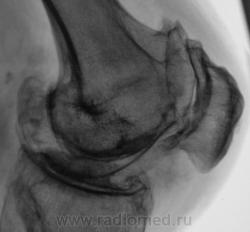

Боли в коленном суставе.

Деформирующий гонартроз 4 ст. или есть какой-то подвох? Двойной контур суставной поверхности медиального мыщелка бедра не Кениг ли случайно?

Мне показалось, что суставная щель вовсе и не так уж сужена.А вот в пателло-феморальный суставе резкое сужение суставной щели.Выраженный субхондральный склероз, краевые остеофиты суставных поверхностей костей.А что там у Косинской по этому поводу написано, помните?

Н.С. Косинская - уже в прошлом (с уважением)... Понятно, что здесь первоочередным критерием являются деформирующие (обезображивающие)

остеофиты, а не ширина суставной щели; и суставные концы костей уплощены ("просели" за счёт остеопороза), и м/мыщелковые бугорки сглажены (бывшие остеофиты).

А на Ваш взгляд "это" истинные остеофиты или окостенение мягкотканных компонентов?